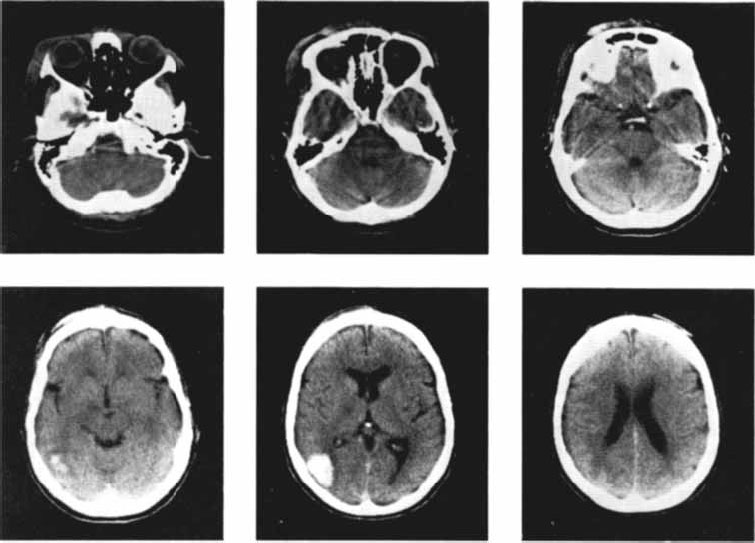

Для улучшения качества изображения перед исследованием пациенту вводят контрастное вещество. Особенно эффективна компьютерная томо графия для исследования повреждений мозга, например, вследствие инсульта (рис. 2.15), рассеянного склероза, опухолей. Кроме очевидной необходимости этого метода для хирургического исследования перед операциями он представляет значительный интерес для психофизиологов и нейрофизиологов, которые изучают когнитивные процессы и поведение людей, имеющих повреждения мозга.

Информативность томограмм увеличивается благодаря применению контрастных веществ, например, верографина (препарата, содержащего йод). Полученная информация в виде снимков может храниться на магнитных носителях, что позволяет пересылать их по каналам компьютерной связи на любые расстояния для консультации специалистов (Лалаянц, Милованова, 1991).

Рис. 2.15. Снимки мозга больных, перенесших инсульт на правой половине мозга, полученные с помощью метода компьютерной томографии (Carlson, 1992).